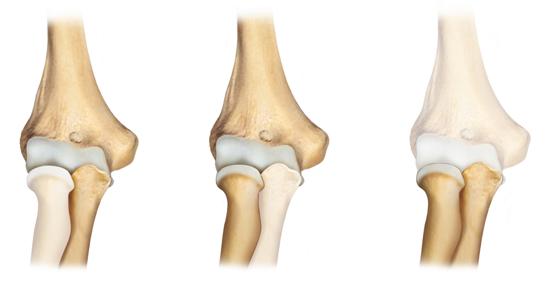

Cenni di anatomia

L’articolazione del gomito è formata da 3 diverse articolazioni (fig.1) che insieme concorrono a determinare i movimenti di flesso-estensione e prono-supinazione, fondamentali per gestire al meglio i movimenti della mano nello spazio circostante.